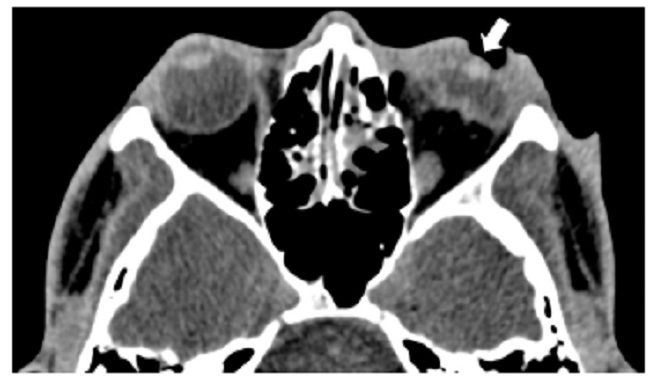

Las calcificaciones oculares y el material médico se pueden confundir con cuerpos extraños u otras lesiones orbitarias1. Las localizaciones típicas de las calcificaciones permiten diferenciarlas de cuerpos extraños hiperdensos. Las más frecuentes son las calcificaciones trocleares, las placas esclerales, las drusas del nervio óptico y la ptisis bulbi. Las primeras tienen localización superomedial dentro de la órbita (Fig. 13), en la tróclea del músculo oblicuo superior, aunque se pueden observar en todas las edades, hay mayor prevalencia de calcificaciones trocleares en pacientes con enfermedades autoinmunes y niveles elevados de fosfatasas alcalinas. Las placas esclerales se localizan en los sitios de inserción de los músculos rectos medial y lateral (Fig. 14) y son más comunes en los pacientes ancianos. Las calcificaciones que ocurren cerca del disco óptico se conocen como drusas del nervio óptico (Fig. 15), las cuales se asocian a degeneración macular y pueden ser causa de pseudopapiledema benigno. La ptisis bulbi es una atrofia y calcificación del globo ocular como secuela de enfermedades infecciosas, inflamatorias o traumáticas previas (Fig. 16) (1,11. Los imitadores de lesiones abiertas del globo ocular incluyen las deformidades como coloboma, estafiloma y el globo ocular elongado por glaucoma o miopía (Fig. 17). Las masas orbitarias y los hematomas también pueden alterar el contorno del globo ocular y asociarse a calcificaciones o relacionarse con desprendimiento de retina (Fig. 18) (1,6,8,11.